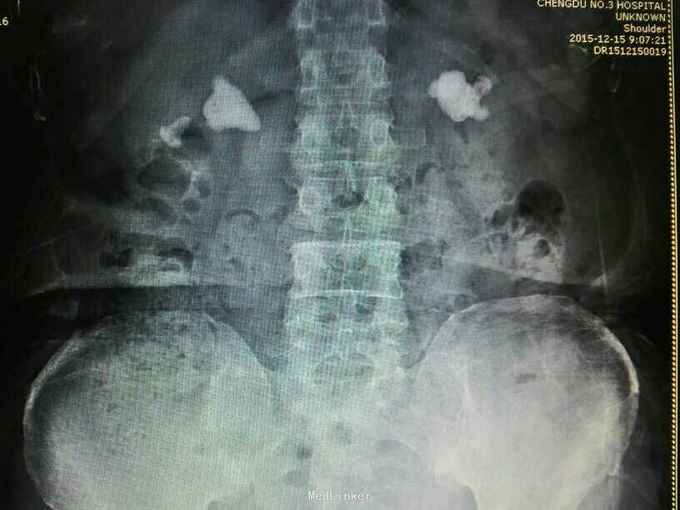

双肾铸型结石伴左肾萎缩一例

72岁男性,因“体检发现双肾结石1月”。既往10年前因双肾结石行双侧肾盂切开取石术(具体不详)。4年前因右肾输尿管结石行右侧输尿管碎石术。

双肾区叩痛。尿常规白细胞1500个/ul,两次尿培养阴性。左肾GFR15右侧38.9。

双肾铸型结石 左肾萎缩,尿路感染,双肾盂切开取石术后,BPH。经抗感染等治疗后,现在尿常规白细胞395.4个/ul。